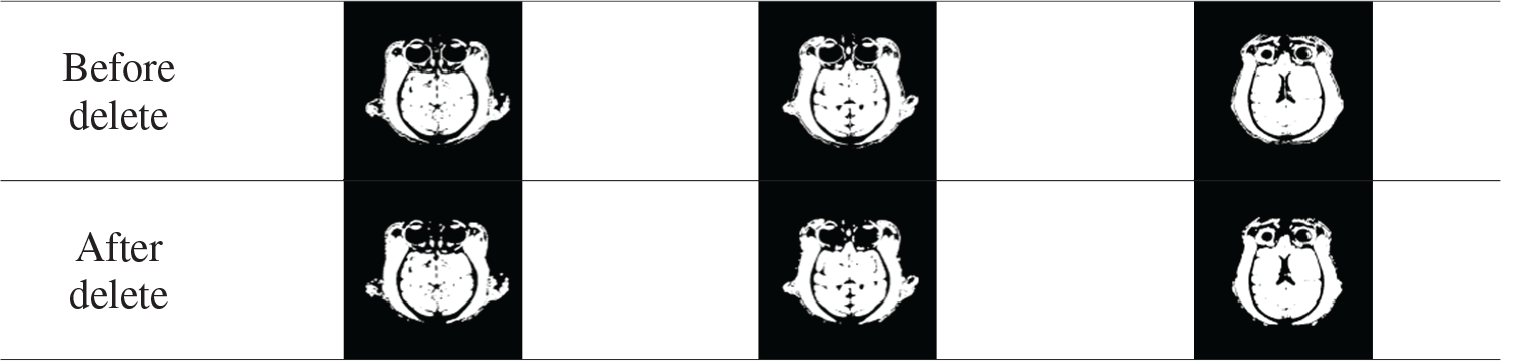

Tab. 1 shows the comparison results before and after deleting small connected regions. This step removes tissue such as the muscles around the eye and simplifies the calculation.

Table 1: Remove small area connectivity region results